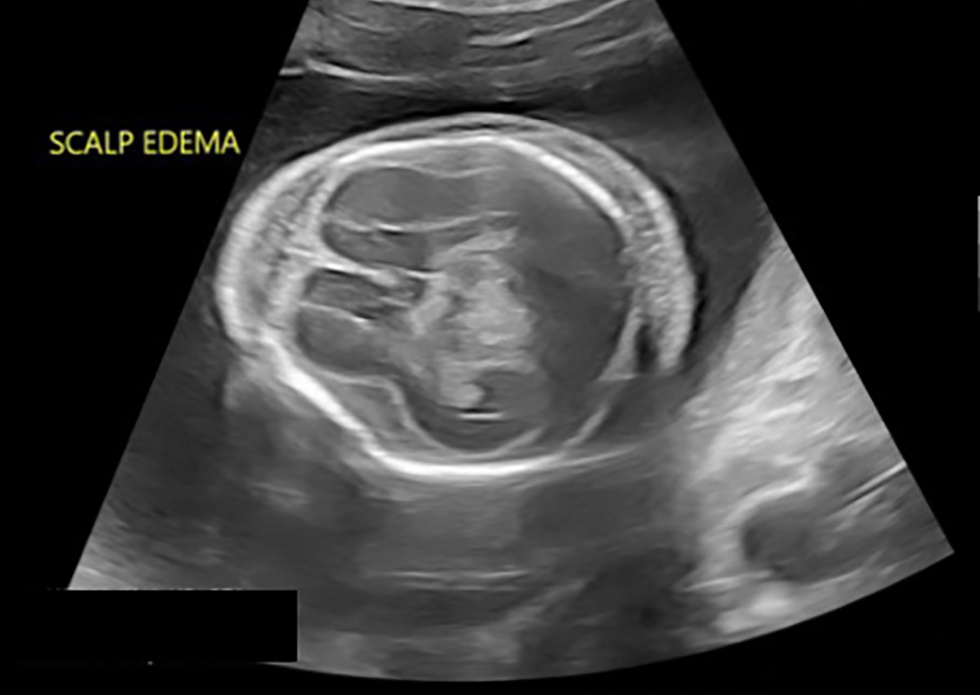

L'échographie réalisée en médecine fœtale-maternelle a démontré une grossesse intra-utérine vivante à l'âge gestationnel de 19+3 semaines. Le fœtus a été affecté par l'hydrops fetalis grave, comme en témoignent les grandes effusions pleurales, de grandes ascites qui compressent les reins et l'œdème de la paroi corporelle (figure 1). Le cerveau était très anormal avec un liquide céphalo-rachidien clair et des échos rayés dans tout le cortex (figure 2). Il y avait des polyhydramnios avec une poche verticale maximale de 8 cm, accompagné d'un placenta épais et ouvertement hydropique (figure 3). L'échographie Doppler de l'artère ombilicale était anormale avec un rapport systolique-diastolique accru. Cependant, le Doppler de l'artère cérébrale moyenne n'a pas démontré d'anémie fœtale (vitesse systolique de pointe 1,37 MoM). Pour effectuer l'évaluation de l'hydrops fetalis, une amniocentèse a été effectuée et elle a été envoyée pour une évaluation microbiologique et génétique. Les résultats sont résumés dans le tableau 2 et le test PCR était entre autres positif pour T. pallidum.

Figure 2 : Œdème marqué au cuir chevelu, cerveau très anormal avec un liquide céphalo-rachidien clair, échos rayés dans toute la matière cérébrale à l'âge gestationnel de 19+3 semaines

Description textuelle : Figure 2

Image par échographie, prise à l'âge gestationnel de 19+3 semaines. Vue en coupe transversale du crâne, au niveau du cavum du septum pellicidum. Il y a de l'œdème marqué au cuir chevelu et la matière cérébrale à une apparence très anormale avec des échos rayés dans tout le liquide céphalo‑rachidien clair.